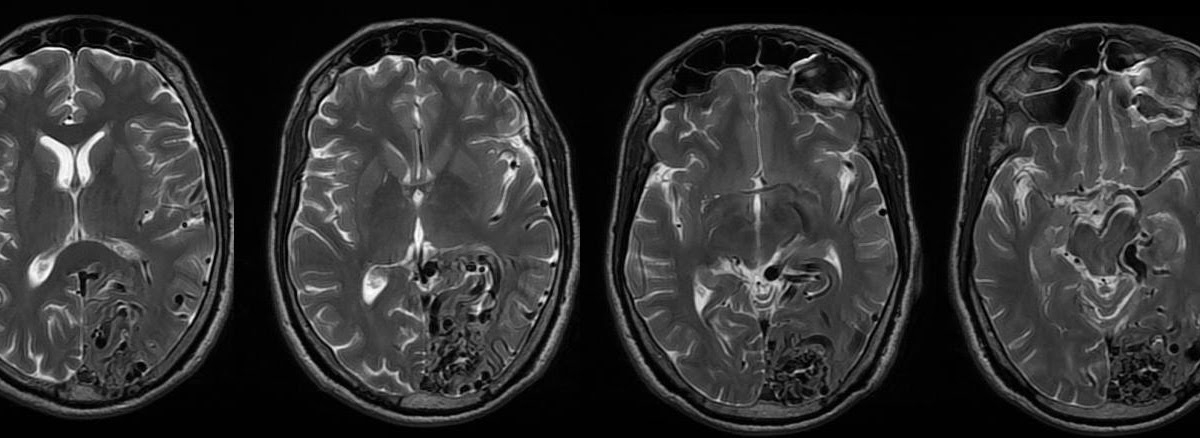

Мр картина венозной ангиомы левой гемисферы мозжечка - 96 фото